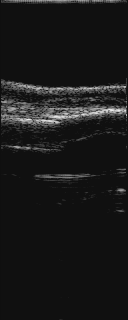

腓骨下端部骨折

61歳 女性

山登りで転倒負傷

右足関節部に腫脹がみられる

エコ−長軸画像

@は、患側腓骨の外側より長軸にプロ−ブをあてた

@では、健側に比べ、骨折しているのがわかる

腫脹もみられる